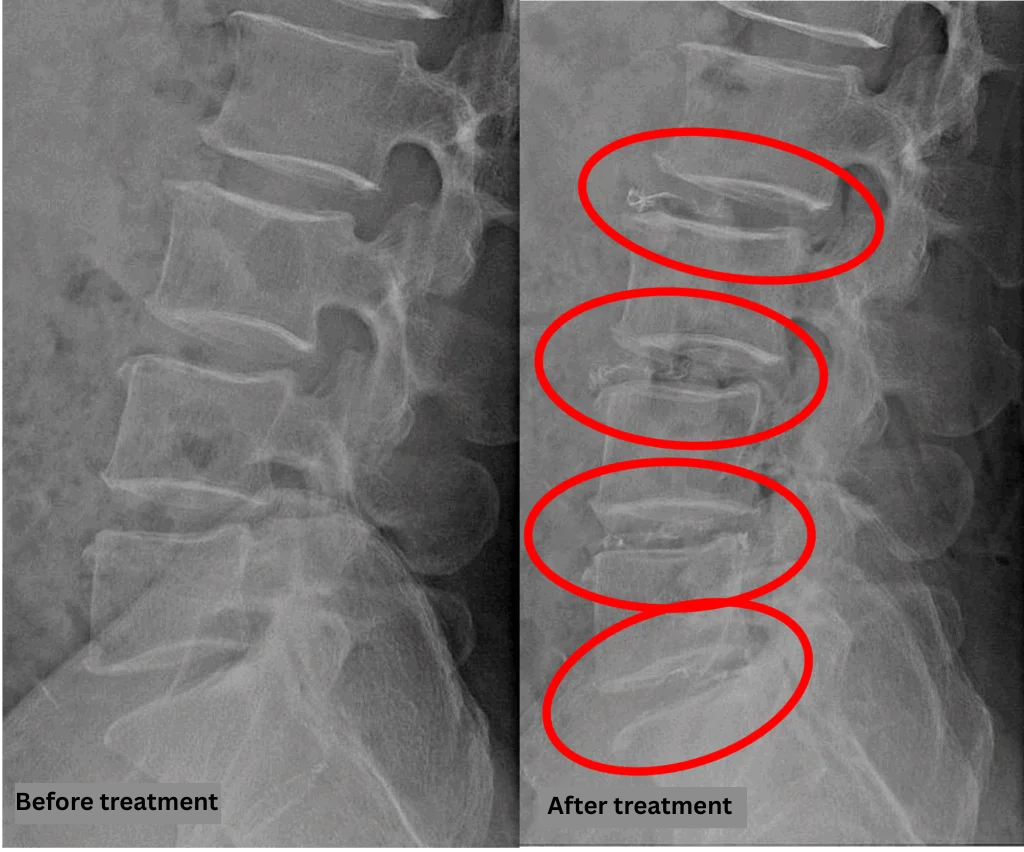

Imaging and findings

- L2/3, L5/S1: Disc degeneration, disc bulging, foraminal stenosis

- L3/4, L4/5: Disc degeneration, lumbar disc herniation, foraminal stenosis

The above findings were also observed on the imaging.

Compression of the spinal canal caused by disc pathology at L2/3, L3/4, L4/5, and L5/S1 was considered the most likely cause of the patient’s symptoms.

After consulting with the patient, the Cellgel Method was performed on L2/3, 3/4, 4/5 and 5/s.